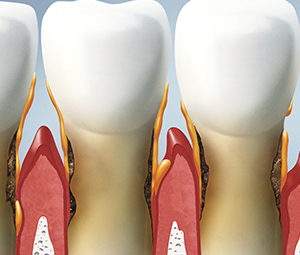

A periodontális betegség - a leggyakoribb patológia, amelyek elfoglalják vezető pozíciókat követően azonnal szuvas. Fogorvosi azt mutatja, hogy a korábbi a betegséget észlel, annál jobb a prognózis. Mert mindannyian tudjuk, hogy a futás ínybetegségek vannak tele a fogak elvesztését.

A működési elve az egység alapja az ultrahanggal. Azonban, ellentétben a klasszikus ultrahang Vector puhább intézkedéseket. Ez kevésbé traumatikus a gumik, nem károsítja a fogzománcot, és nem okoz fájdalmat.

Indikációk Vector készülékek - elsősorban a gyulladásos betegségek kezelésére periodontiumban és eltávolítását foglepedék szilárd.

Köszönhetően a lágy tápegység, kemény és lágy részecskék könnyen eltávolítható a ínytasakokat. Ez is hozzájárul a speciális gél, amelyet az eljárás során. Kiküszöböli az érdesség, hogy jelen volt, mielőtt, a baktériumok száma jelentősen csökken.

Periodontális betegségek kezelésére végezzük módon egy speciális szerszámmal Vector Scaler. Annak a ténynek köszönhetően, hogy a folyadék áthalad a gép belsejében, nincs gyors kialakulását aeroszol. Ebben az esetben fennáll annak alkalmazásának lehetőségét zagy fényezésére. Az energia az ultrahang hullámok fokozódik eredményeként alkalmazása kerámia lemezeket. Ez hozzájárul a gyors és hatékony felszámolását szilárd dentális plakk. A baktériumokat eltávolítjuk még a távoli helyeken, amely kiterjeszti a készülék alkalmazása. A megkülönböztető jegye a készüléket a klasszikus ultrahang, hogy az eszköz nem karcolja, és nem károsíthatja a gyökereket, gyengéden polírozza nekik, hogy eltávolítja a durvasága és ad simaságát.